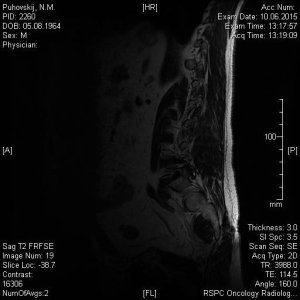

Сегодня сделали МРТ поясничного отдела позвоночника моему отцу. Результат записан на СD диск с множеством фото, заключение, соответственно, прилагается. Но для полной уверенности хотелось бы подтверждения иного специалиста. Основные симптомы: острые и постоянные боли в пояснице, периодически "отказывают" ноги (приходится постоянно менять свое положение-присесть, выгнуться, нагнуться, пройтись и т.п). Не маловажный факт, что около 5 лет назад с идентичными симптомами у папы обнаружили грыжу и удалили ее. Опыт имеется, а страх все равно присудствует. Помогите пожалуйста.

image.jpg32 КБ · Просмотры: 678

12.jpg48,8 КБ · Просмотры: 638

11.jpg48,3 КБ · Просмотры: 707

10.jpg48,1 КБ · Просмотры: 764

9.jpg49,7 КБ · Просмотры: 764

8.jpg31,9 КБ · Просмотры: 666

7.jpg32 КБ · Просмотры: 671

6.jpg43,3 КБ · Просмотры: 592

5.jpg31,9 КБ · Просмотры: 640

4.jpg33,3 КБ · Просмотры: 609